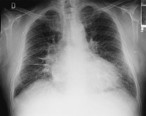

- Radiografía de tórax

• Cardiomegalia.

• Signos de congestión pulmonar:

• Fases iniciales: patrón venoso.

• Fases avanzadas: patrón alveolar.

Stacks Image 3242

Seleccione la imagen para ampliar.